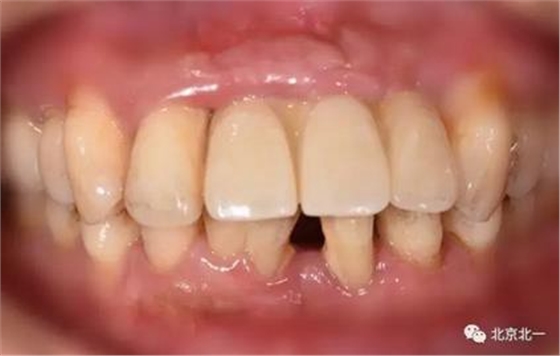

圖六:戴牙后口內(nèi)照,患者笑線低。未做牙齦誘導(dǎo)也不太影響容貌。簡(jiǎn)化治療程序節(jié)省患者時(shí)間成本以及金錢(qián)成本。

圖七:微笑時(shí)照片